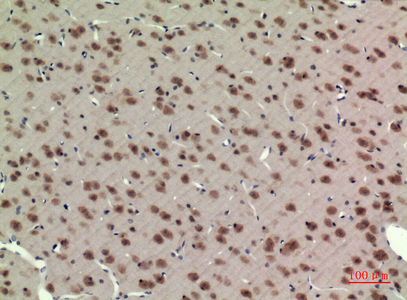

IHC 1/50-1/100 Human,Mouse,Rat

ImmunogenThe antiserum was produced against synthesized peptide derived from human BMAL1 around the non-acetylation site of Lys538. AA range:501-550

BMAL1 antibodies are critical tools for studying circadian biology and related pathologies. They are widely used in techniques like Western blotting, immunofluorescence, immunohistochemistry, and chromatin immunoprecipitation (ChIP) to detect BMAL1 expression, localization, and DNA-binding activity. These antibodies help researchers explore tissue-specific circadian rhythms, dysregulation in metabolic disorders (e.g., diabetes), sleep disorders, and cancer. Commercially available BMAL1 antibodies vary in host species, clonality, and epitope specificity, with validation in knockout models being crucial for confirming reliability. Recent studies also utilize BMAL1 antibodies to investigate time-restricted feeding, jet lag mechanisms, and chronotherapy applications, highlighting their versatility in bridging molecular clocks to human health.